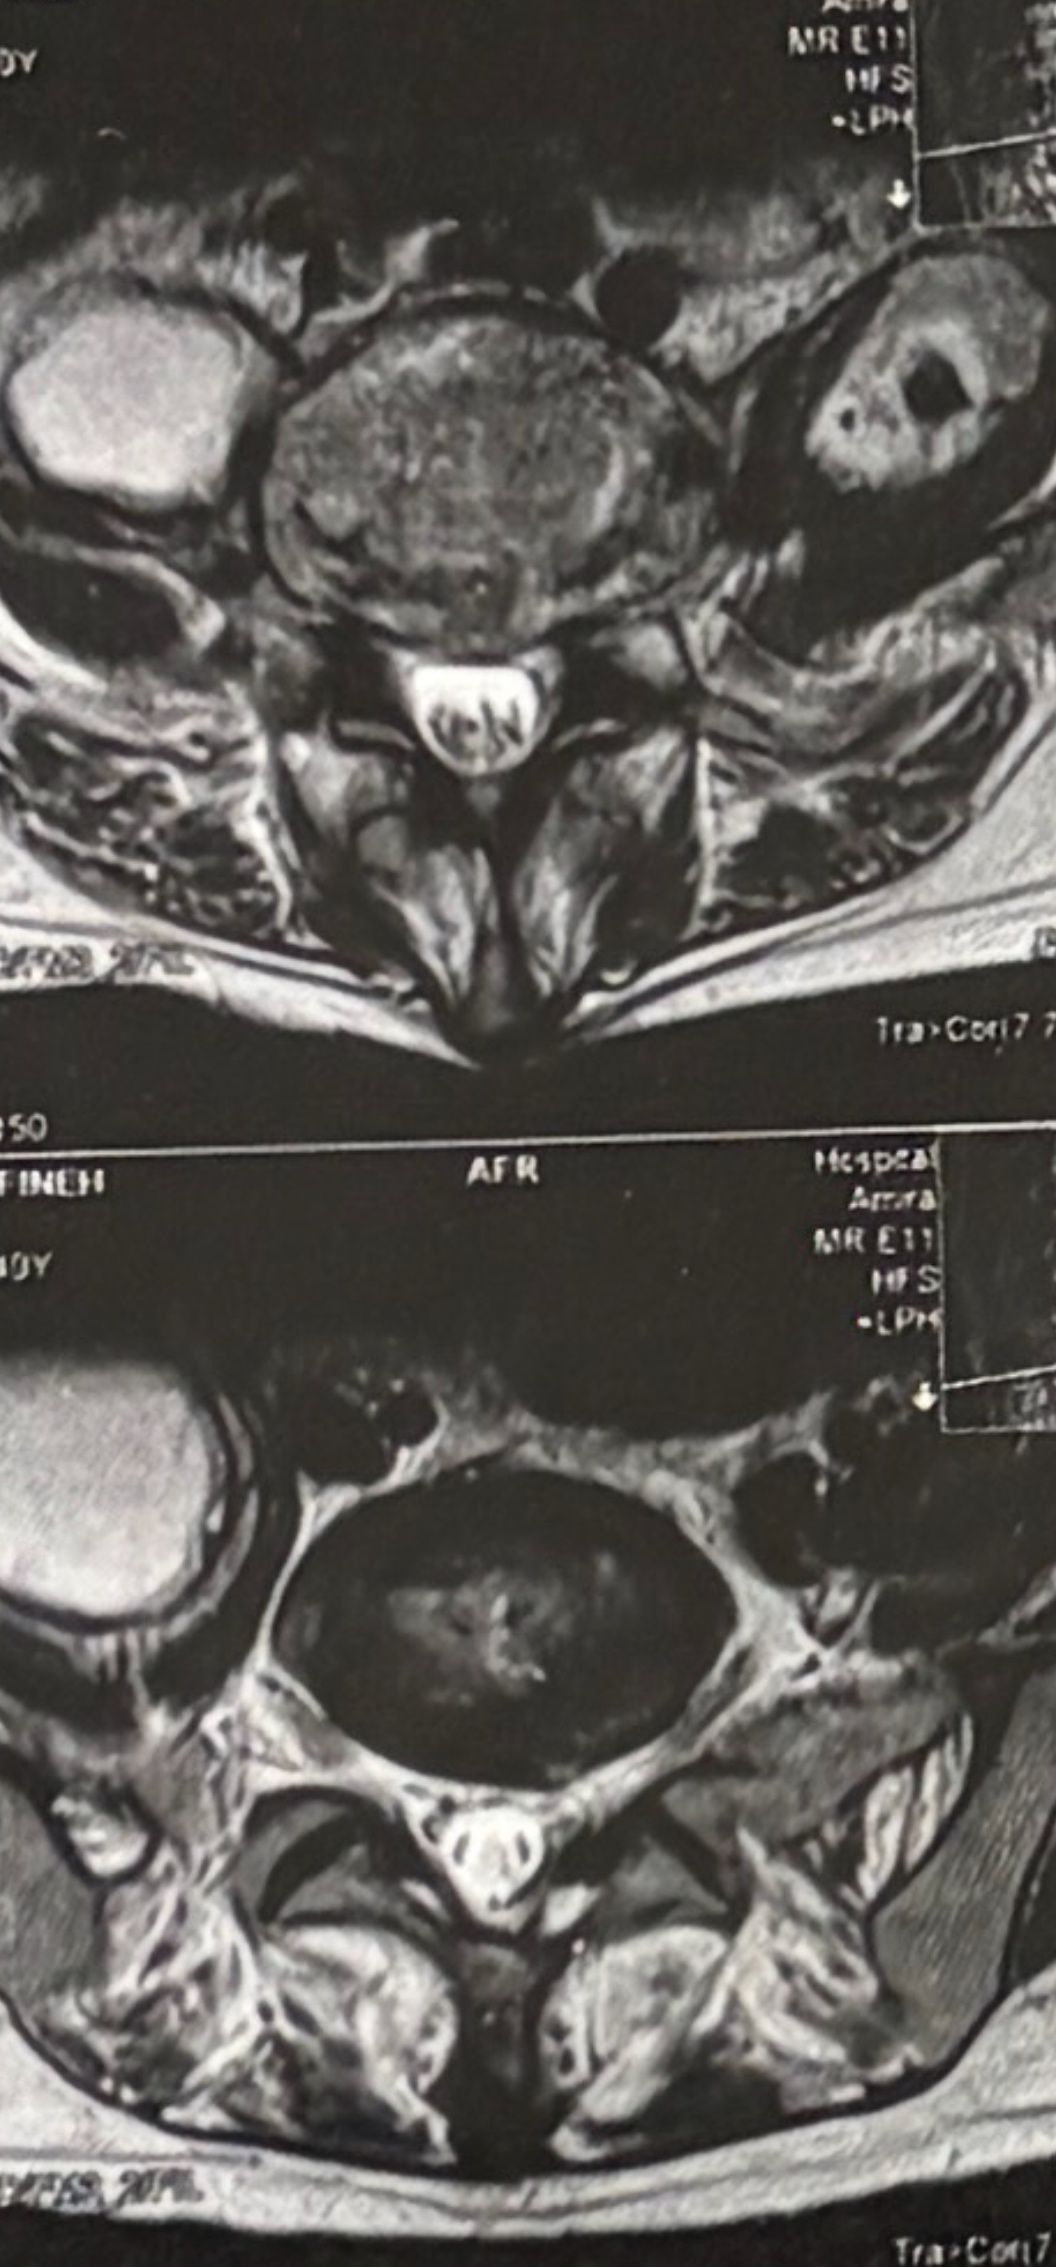

40 yrs old male patient presented to my office who had severe R gluteal pain and radicular pain along R L5-S1 now pain has reduced by 80% in his motor exam had R big toe L5 motor reduced to 4+\5 and R S1 DTR was 0 while L S1DTR was 1+

We did EMG/NCV which showed Mod- sever R L5 S1 irritation without any active axonal loss

I had to decide to refer him for surgery or not patient didn’t have any treatment meanwhile

I ordered new L/S mri

I posted his new mri and old mr

Which was 20 days ago and have posted all below

The first 12 mris had been done 20 days ago

After those first 12 MRIs i have posted new MRIs which were done yesterday

After seeing his new mri and emg/ncv and getting sure his neurological deficit is not active and progressing i told patient he doesn’t need surgery at this time and released him with some advices and exercises